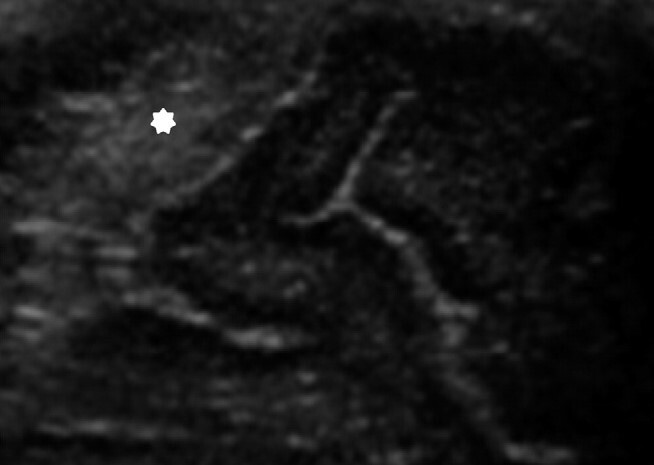

Neonatology Pseudo-hemorrhage Image